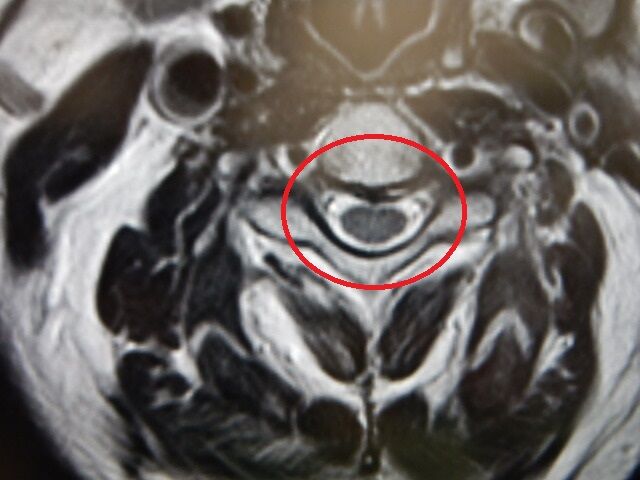

ç¹Â¡ÉÕ¶á¤ÎÆæ¤ÎO¥ê¥ó¥°

Á°²ó;¤ê¤ÎÄˤµ¤«¤é³Ý¤êÉÕ¤±°å¤Ø¹Ô¤¶ÛµÞ¤ÇCT»£±Æ¤ò¤·¤ÆÌã¤Ã¤¿²èÁü¤ÎµÏ¿¤ò

;¤ê¤Î¥·¥ç¥Ã¥¯¤«¤é¼Ì¿¿»£±Æ½ÐÍè¤Ê¤«¤Ã¤¿¤Î¤Ç

ºòÆü¤Î¼õ¿Ç»þ¤Ë¼ç¼£°å¤Ë¤ª´ê¤¤¤ò¤·¤Æ

²èÁü¤ò½Ð¤·¤Æ¤â¤é¤¤¡¢¼Ì¿¿»£±Æ¤ò¹Ô¤Ã¤Æ

ÀâÌÀ¤â¤Á¤ã¤ó¤Èʹ¤¤¤Æµï¤Ê¤«¤Ã¤¿¤Î¤Ç

ÁÛÄêÉÂ̾¤òʹ¤¤¤Æ¡¢º£¸å¤Î¼£ÎÅÊýË¡¤âÁêÃ̤·

©»Ò¤Ë¤â²èÁü¤òÁ÷¿®¡¢Â©»Ò¤Î¿ÇÃÇ·ë²Ì¤âƱ¤¸¤Ê¤Î¤Ç¤¹¤¬

¼ç¼£°åƱÍÍ¡¢²èÁü¤«¤éȽÃǤ¹¤ë±ê¾É¤ÎÅٹ礤¤¬Ä㤤¤È¸À¤¦¡Ä

¼è¤ê¹ç¤¨¤º»à¤Ì»ö¤Ï̵¤µ¤½¤¦¤Ê¤Î¤Ç¡¢ÄˤߤϲæËý¤¹¤ë»ö¤Ë¤·¤Þ¤¹¡ª

¼ç¼£°å¤Î¿ÇÃǤÈ©»Ò¤Î¿ÇÃÇ¤ÏÆ±¤¸¸«²ò¤ÇÉÂ̾¤ÏÂçIJ¤Î¡Ö·Æ¼¼±ê¡×¤È¸À¤¦»ö¤é¤·¤¤¡Ä

²Ç¤Ï£Ï¥ê¥ó¥°¤ò°û¤ß¹þ¤ó¤À¤Î¤«¤È»×¤Ã¤¿¤é¤·¤¤¤ï£÷